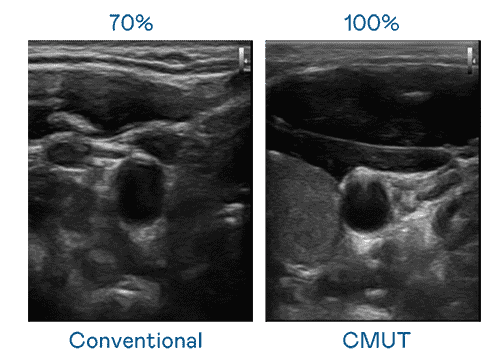

CMUT 技术是一种用电容式微机电元件来产生超音波讯号的技术。。与传统 PZT 压电式技术相比,,,CMUT 频宽增加 30%,,,更宽频的超音波讯号让影像解析度大幅提升,,,,是实现高影像品质医疗超音波扫描、、、、促进精准医疗发展的关键技术。。。

超音波影像的解析度高低,,首先取决于探头能发出的讯号频宽。。。。尊龙集团 CMUT 可提供高清晰的超音波讯号,,提供高频宽、、高灵敏度、、影像纹理细节更高的超音波影像,,,,协助医护人员缩短影像判读时间及利用精准的医疗影像进行诊断。。。。